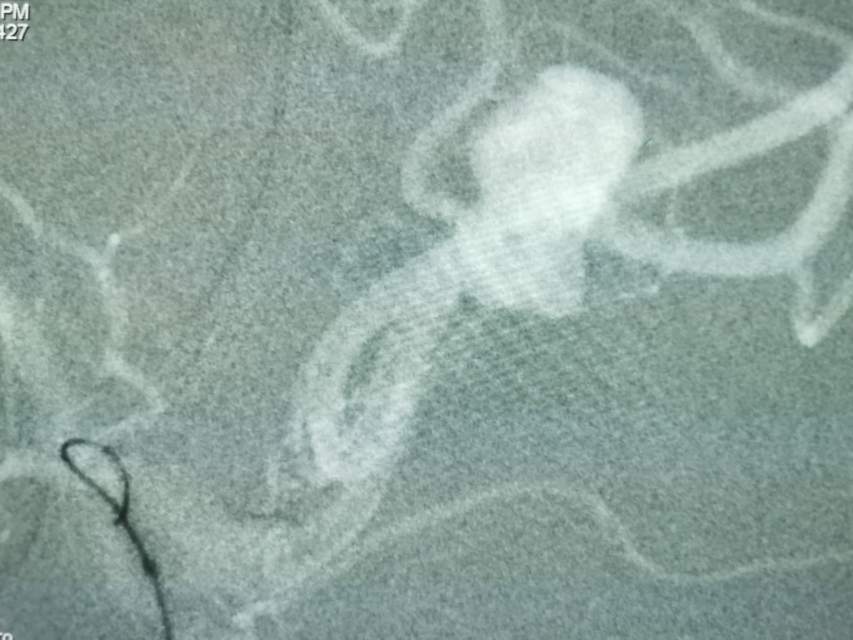

福建中年女性,近期在外查出“颅内动脉瘤”,经推荐转来我院诊治。患者的颈内动脉通路迂曲,动脉瘤也位置奇特,解剖复杂,动脉瘤远近段的血管弯弯绕绕,重重叠叠,眼花缭乱,难以兼顾找到最佳位置。最终克服困难,将“基底型”动脉瘤改变为“侧壁型”动脉瘤,顺利给予治疗……